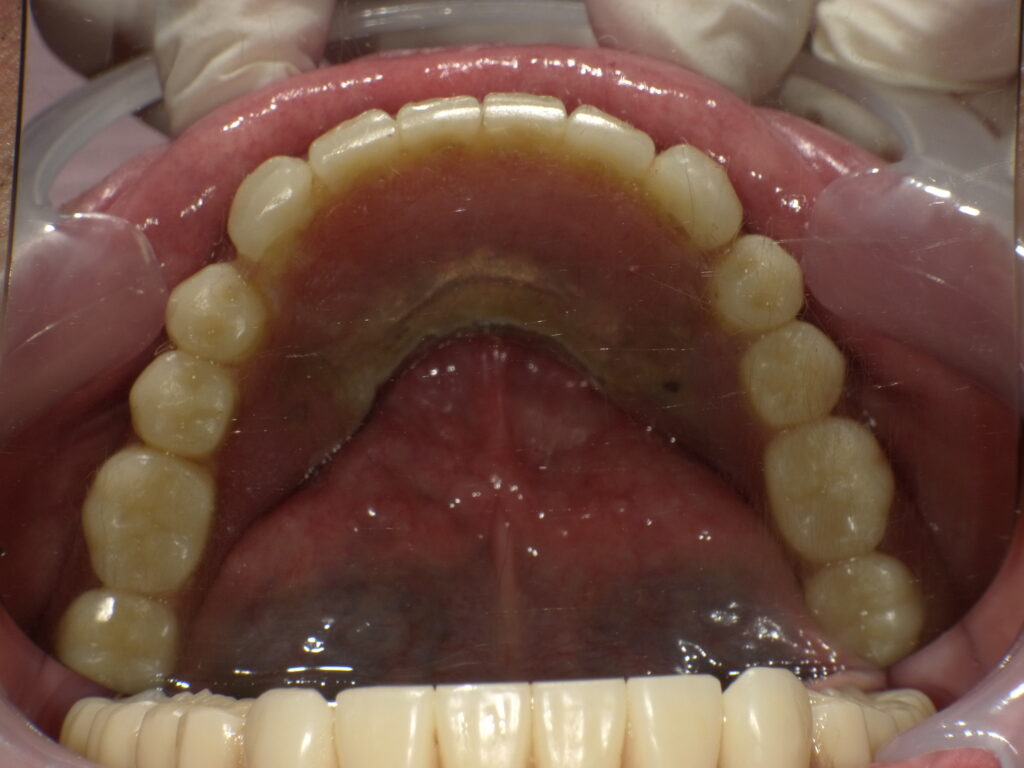

症例一覧 インプラントロケーター義歯症例1 2025.12.18 user comment…. user comment…. 治療内容インプラントロケーター義歯治療期間準備中 ホワイトニング症例4 前の記事 ワンデーTREATMENT(セレック治療)症例1 次の記事